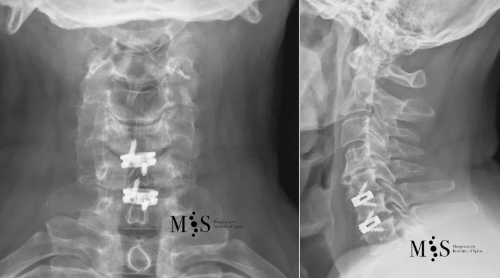

Post-operative X-rays showing an interbody cage at two separate cervical disks after placement with endoscopic fusion surgery

of the cervical spine and was discharged from the hospital in less than 24 hours after surgery.

This 49 years-old patient presented with a migrated cervical herniation at level C4/C5 and an unstable disk at C5/C6. En endoscopic cervical decompression was performed to remove the herniation and two intervertebral cages were placed endoscopically using a a skin incision of just 2 cm length. Post-operatively, the patient recovered very quickly and was discharged from the hospital within a day after surgery.